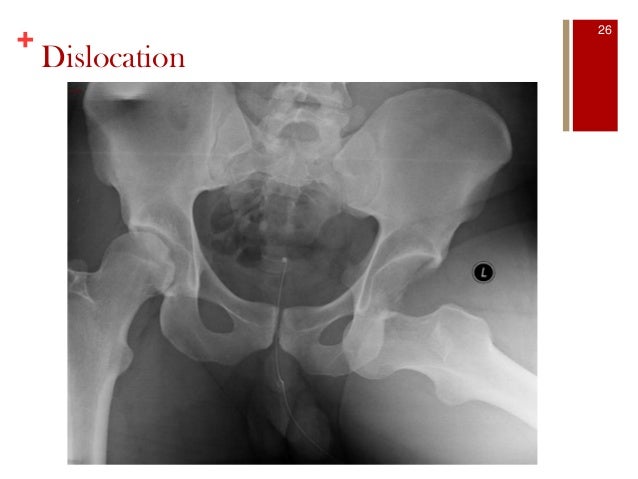

23. 23. + Dislocation 26